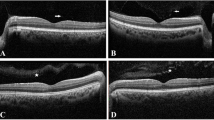

The most common oldest chelating agent in β-thalassemic patients is intravenous DFO therapy. DFO toxicity has led to nyctalopia, color vision deficiency, visual field defects, visual acuity impairment, and RPE changes [41, 64]. There is significant correlation between DFO dosage and its ocular side effects. In most studies, when patients were on DFO with dosage of less than 50 mg/kg/d, mild or no ocular toxicities have been reported [17, 65]. Some studies have revealed that the retinal toxicity due to intravenous DFO therapy is reversible to some extent after discontinuing the drug [66, 67]. Therefore, it is essential to perform ocular examinations by implementing different methods such as electrodiagnostic procedures (especially ERG), visual field testing, color vision testing, confocal near-infrared (NIR) reflectance imaging, fundus fluorescein angiography (FFA), late-phase indocyanine green (ICG) angiography, fundus autofluorescence (FAF), and spectral domain optical coherence tomography (SD-OCT). Table 3 summarizes previous retinal findings with different imaging techniques in β-thalassemia patients who were under chelation therapy [14, 42, 45, 68,69,70,71,72,73,74].

Viola et al. [45] used multimodal imaging such as confocal scanning laser ophthalmoscope (cSLO), NIR, FAF, and SD-OCT to investigate and follow up clinical course of β-thalassemia patients with DFO retinopathy. They found pattern dystrophy-like changes in half of their patients. Follow-up examinations of their patients during a 40-month period revealed a progressive development of RPE atrophy in most of their cases. Therefore, in cases requiring long-term treatment with chelator drugs, observing early changes such as pattern dystrophy-like alterations in deep structures of the retina could predispose sight-threatening complications such as RPE atrophy [45]. Therefore, early diagnosis and long-term follow-up of retinal findings, either PXE-like or related to DFO, are essential and would be helpful in the decision to discontinue or switch therapy to prevent sight-threatening ocular problems.

A closer look at the literature on ERG and EOG, however, reveals a number of gaps and shortcomings. To date, this is not clearly stated in the literature whether ERG and EOG tests could show any signs before FFA and SD-OCT clinical manifestations. However, it is prudent to pay attention to the results of these tests and use them as a clinical guideline before retinal manifestations [41, 100]. Many studies have highlighted the importance of EOG test. They have emphasized that decline in Arden ratio in EOG is extremely beneficial since majority of complications related to iron overload occur in RPE layer [100, 101]. In contrast, some other studies have reported normal EOG findings in β-thalassemic patients [91]. Kertes et al. introduced multifocal-ERG as an effective method in the diagnosis of maculopathies resulted from DFO toxicity [102]. They reported depression of responses, especially in central areas, and the results were consistent with previous research [89, 102]. Studies have made a comparison between oral iron chelator and DFO. It was found that electrodiagnostic findings related to DFO show a greater decrease than oral iron chelator group. It was observed more in the figures related to wave latency in comparison with wave amplitude [89].

Another clinical test for the investigation of early ophthalmic manifestations of β-thalassemia and its management strategies is FAF. Abnormal fluctuations in FAF have been reported in these patients prior to observable changes in fundus examination. This is an effective, fast, and noninvasive method for monitoring retinal involvement in these patients [43, 45, 74]. FAF using short-wavelength light mainly originates from the RPE and is useful for detecting secondary changes within this layer [45].

Other methods that could be particularly helpful in the early diagnosis of β-thalassemia complications are visual field investigation particularly by utilizing advanced technologies like micro-perimeter devices, SD-OCT and confocal near-infrared (NIR) reflectance imaging [43, 45, 70, 108]. Long-wavelength light used in NIR reflectance helps to visualize early alterations occurring within Bruch’s membrane underneath the RPE, which absorbs shorter-wavelengths lights [108]. Since most of the complications related to β-thalassemia are age dependent and appear in people over 20, it would be suggested that regular ocular checkups be performed in their second decade of life. This issue is largely important when PXE-like lesions especially AS are observed in the process of the disease. Moreover, if CNV is formed, we should take treatment actions to prevent retinal hemorrhages and vision loss.

Since life expectancy in β-thalassemic patients has improved over time, the possibility of ocular abnormalities increases. It is demonstrated that primary fundus alterations in β-thalassemia patient’s eyes usually occur in the Bruch membrane and RPE. Abnormalities of these retinal layers are easily detectable using novel noninvasive imaging modalities such as cSLO, NIR reflectance, and FAF imaging even before symptoms are manifested in these patients. Therefore, long-term follow-up of β-thalassemia patients with these new multimodal imaging techniques, especially those who need long-term DFO treatment, is essential and could help to prevent development of further sight-threatening ocular problems by chelation therapy modification.